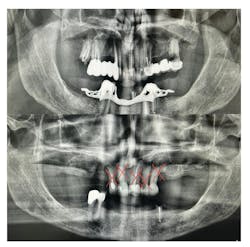

For many older adults, the transition to complete edentulism (figure 1) is both a clinical and emotional hurdle. It often brings feelings of grief, loss of identity, and a gradual detachment from routine dental care. However, this stage should not signal the end of the dental hygienist’s involvement. On the contrary, it requires heightened attention.

While many dental professionals focus on mechanical aspects of dentures—fit, retention, and occlusion—the hygienist’s role extends to soft tissue assessment and early detection of pathology. Some of the most common conditions seen in edentulous patients include (table 1):